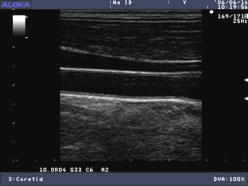

健康な血管(十分に血液が流れる)

• エコー画像

エコー画像:

つまっている血管(血液が流れにくい)